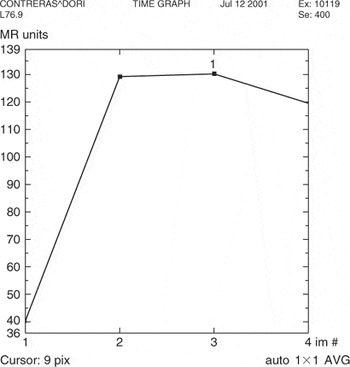

Kuhl et al. [12] described three general types of curves that rely less on the absolute value of the enhancement than on the shape of the enhancement curve. A Type-I curve is continuous enhancement increasing with time (Fig. 22). A Type-II curve reaches a plateau phase where maximum SI is reached approximately 2–3 min after injection and the SI remains constant at this level. Type-III is a washout curve where there has been a decrease in SI after peak enhancement has been reached within 2–3 min (Fig. 23).

Figure 22. Type-I curve demonstrating persistent enhancement. Pathology – Fibroadenoma.

Figure 23. Type-III curve demonstrating washout. Pathology – Invasive lobular cancer.

As a general rule, benign lesions follow Type-I curve and malignant lesions follow a Type-III curve. A Type-II curve can be seen with both benign and malignant lesions. As with morphologic analysis, malignant lesions can exhibit benign kinetics and vice versa. Kuhl et al. [12] showed that 57% of malignant lesions demonstrated a Type-III curve and 83% of benign lesions showed a Type-I or -II curve. In a recent study by Bartella [13], a retrospective review was performed on 68 mammographically occult invasive cancers detected by MRI; only 38% had washout kinetics and the majority 59% had plateau kinetics. It is therefore important to carefully assess the morphologic features in lesions with plateau kinetics.